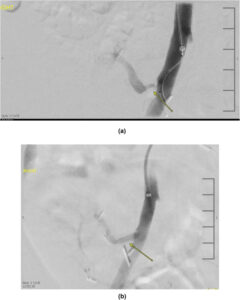

• عنوان: آنژیوگرافی شریانی پیوند کلیه

• توضیح: تصویر آنژیوگرافی شریانی پیوند کلیه که نشان‌دهنده وضعیت عروقی گرافت است.